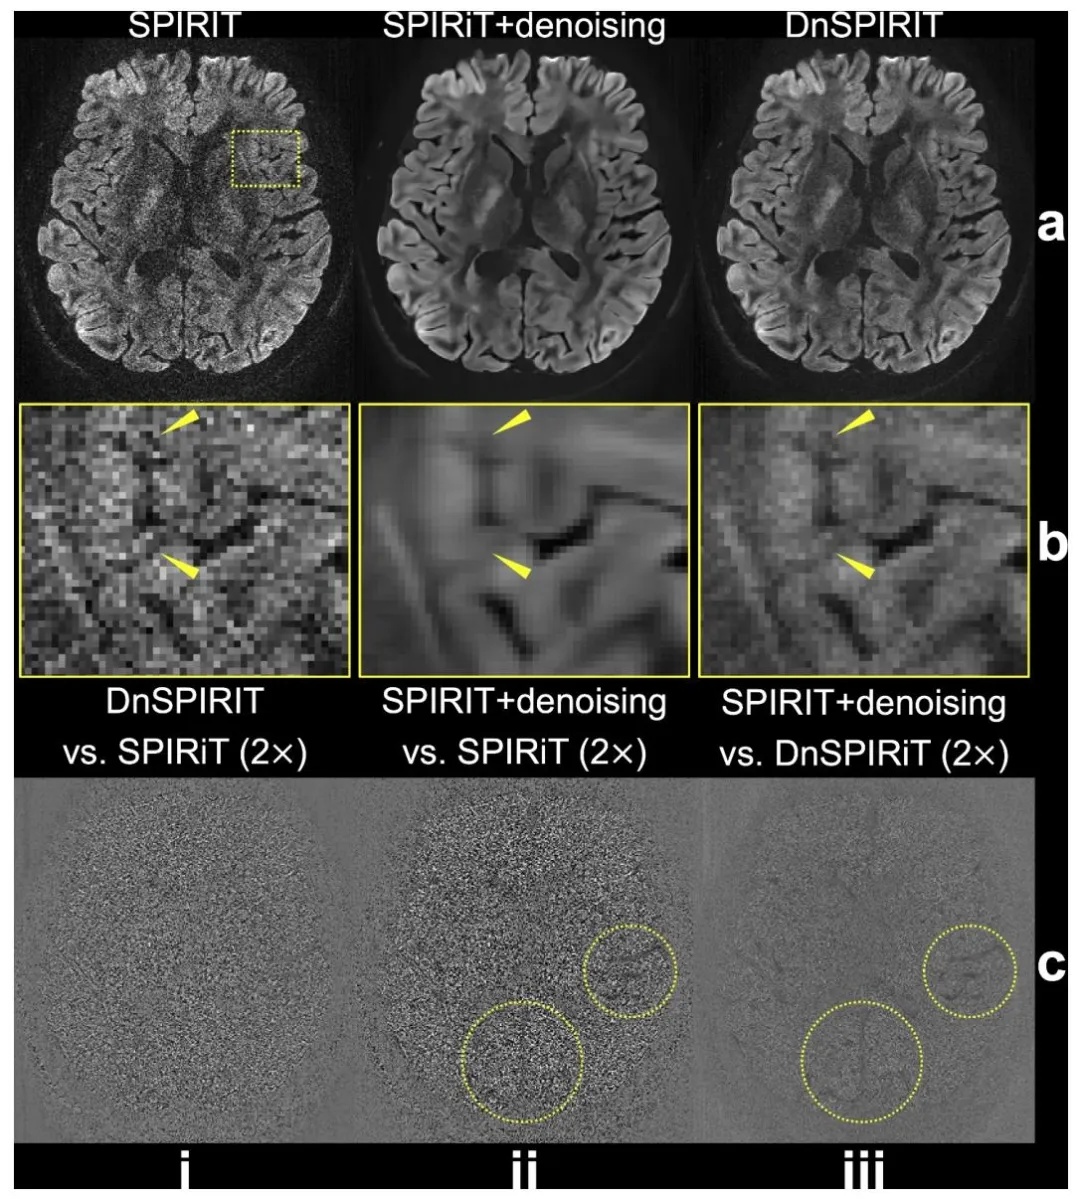

Fig. 2. Comparison of image reconstruction and processing strategies. In-vivo diffusion-weighted data (b = 1000 s/mm2 ) from 3T 0.65 mm protocol along (− 0.45, − 0.83, 0.32) are reconstructed using SPIRiT (a, i), SPIRiT followed by standalone BM4D denoising (SPIRiT+denoising, a, ii), and denoiser-regularized SPIRiT (DnSPIRiT, a, iii), with an enlarged region showing the image detail (b). Yellow arrows indicate regions where anatomical structures appear blurred in SPIRiT+denoising but are better preserved by DnSPIRiT. The difference maps between DnSPIRiT and SPIRiT (c, i), SPIRiT+denoising and SPIRiT (c, ii), SPIRiT+denoising and DnSPIRiT are also shown to illustrate the distribution of noise and structural differences (highlighted by yellow circles) across methods.

图2 图像重建与处理策略对比。基于3T 0.65毫米协议、扩散方向为(−0.45, −0.83, 0.32)的在体扩散加权数据(b=1000秒/平方毫米),分别采用以下三种方式重建:SPIRiT重建(a,i)、SPIRiT重建后进行独立BM4D去噪(SPIRiT+去噪,a,ii)、去噪器正则化SPIRiT重建(DnSPIRiT,a,iii);放大区域展示图像细节(b)。黄色箭头指示SPIRiT+去噪方法中解剖结构出现模糊、而DnSPIRiT方法能更好保留结构细节的区域。同时展示了以下差异图:DnSPIRiT与SPIRiT的差异图(c,i)、SPIRiT+去噪与SPIRiT的差异图(c,ii)、SPIRiT+去噪与DnSPIRiT的差异图,以阐明不同方法间噪声分布及结构差异(黄色圆圈突出显示)。